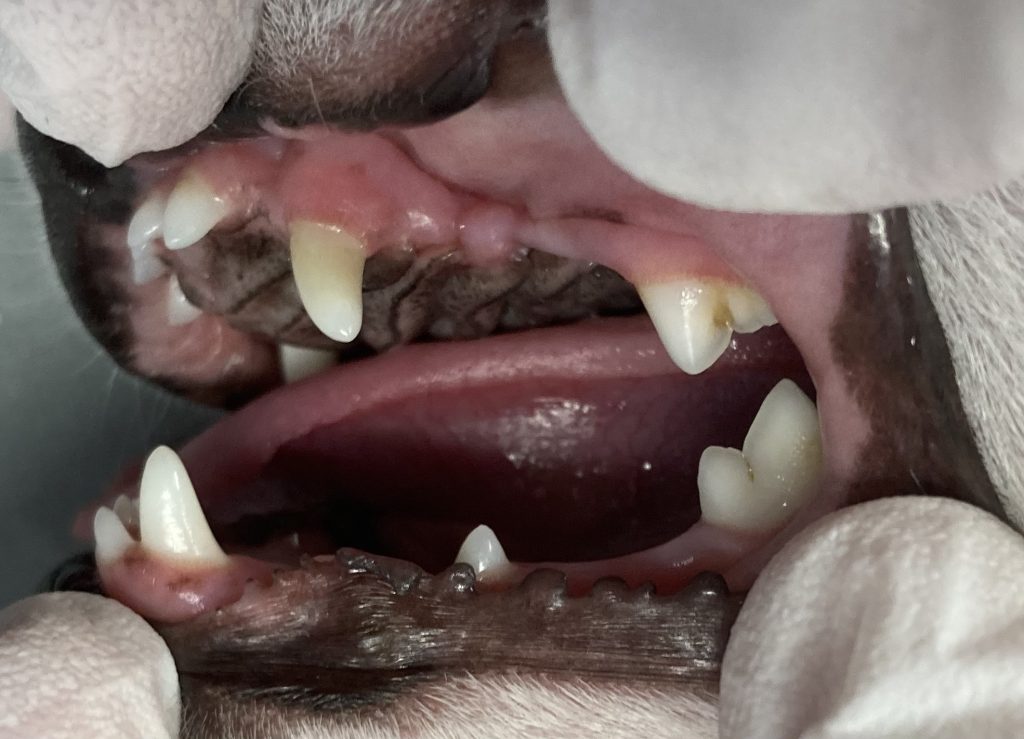

次の写真を見てみましょう。

この症例は歯磨き教室先生から歯が少ないことの指摘を受けて受診されました。

この子は3歳になる成犬ですが、上顎の第一から第三前臼歯と下顎の第一、第二、第四前臼歯が萌出していません。